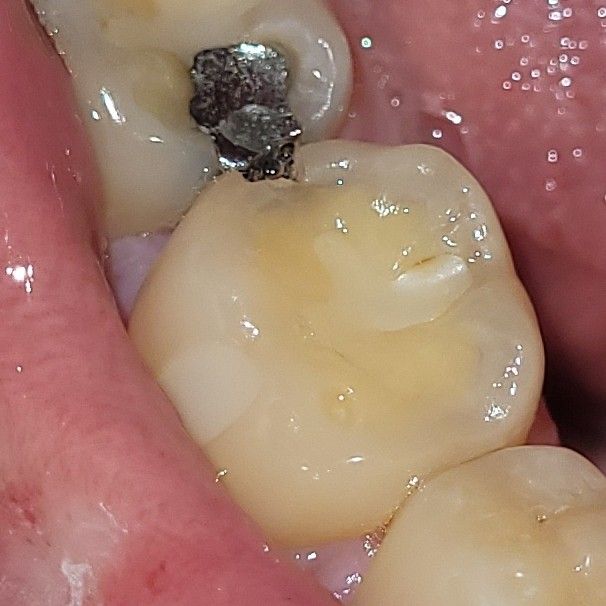

교환학생 중 어금니가 깨졌습니다.ㅠㅠㅠㅠ

스위스에서 교환학생중인데.. 어금니가 깨졌습니다

5개월 뒤 귀국인데, 그 때까지 칫솔 치간칫솔로 관리가 가능할지 궁금합니다

• 1번 째 사진

일단은 치아 사이가 깨진거라서 음식물이 잘낄수 잇으니 일단 양치를 잘하시고 치실이나 치간칫솔로 음식물이 남아 잇지 않도록 관리를 해주시는게 중요합니다.

해당부위로 음식물이 잘 낄 것으로 예상되긴 합니다 워터픽으로 관리하시는 것도 좋을 것 같습니다 딱딱하거나 질긴 음식을 피하세요

어쩔 수 없기 때문에 최대한 해당 치아로 씹는 것은 조심하시고 관리 잘하시다가 치료 받으면 됩니다.

해당부위로 단단하거나, 질긴음식을 씹는 것은 피하여, 추가적인 깨짐이 일어나지 않도록 관리하길 권합니다.